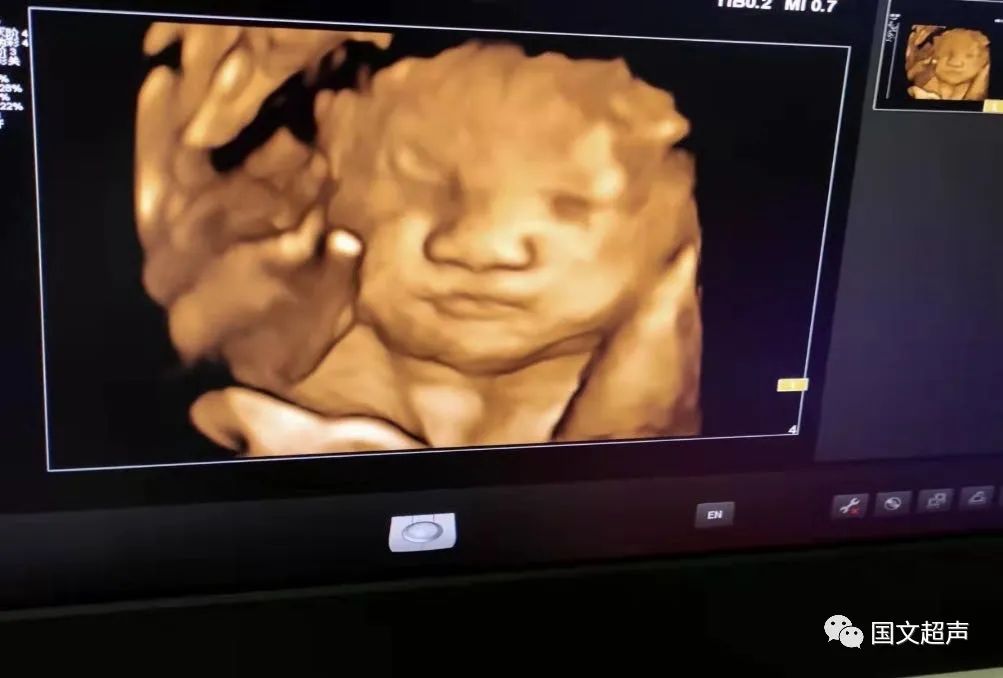

一.飛利浦EPIQ7高端四維彩超

我院目前使用的是飛利浦EPIQ7高端四維彩超,它擁有高品質(zhì)自動成像分析技術(shù),分辨率及清晰度高,可以較清晰的顯示宮內(nèi)胎兒的生長發(fā)育情況,為診斷胎兒先天性畸形,如唇裂、脊柱裂、顱腦發(fā)育異常、骨骼發(fā)育異常、心血管畸形等提供準確的科學依據(jù)。